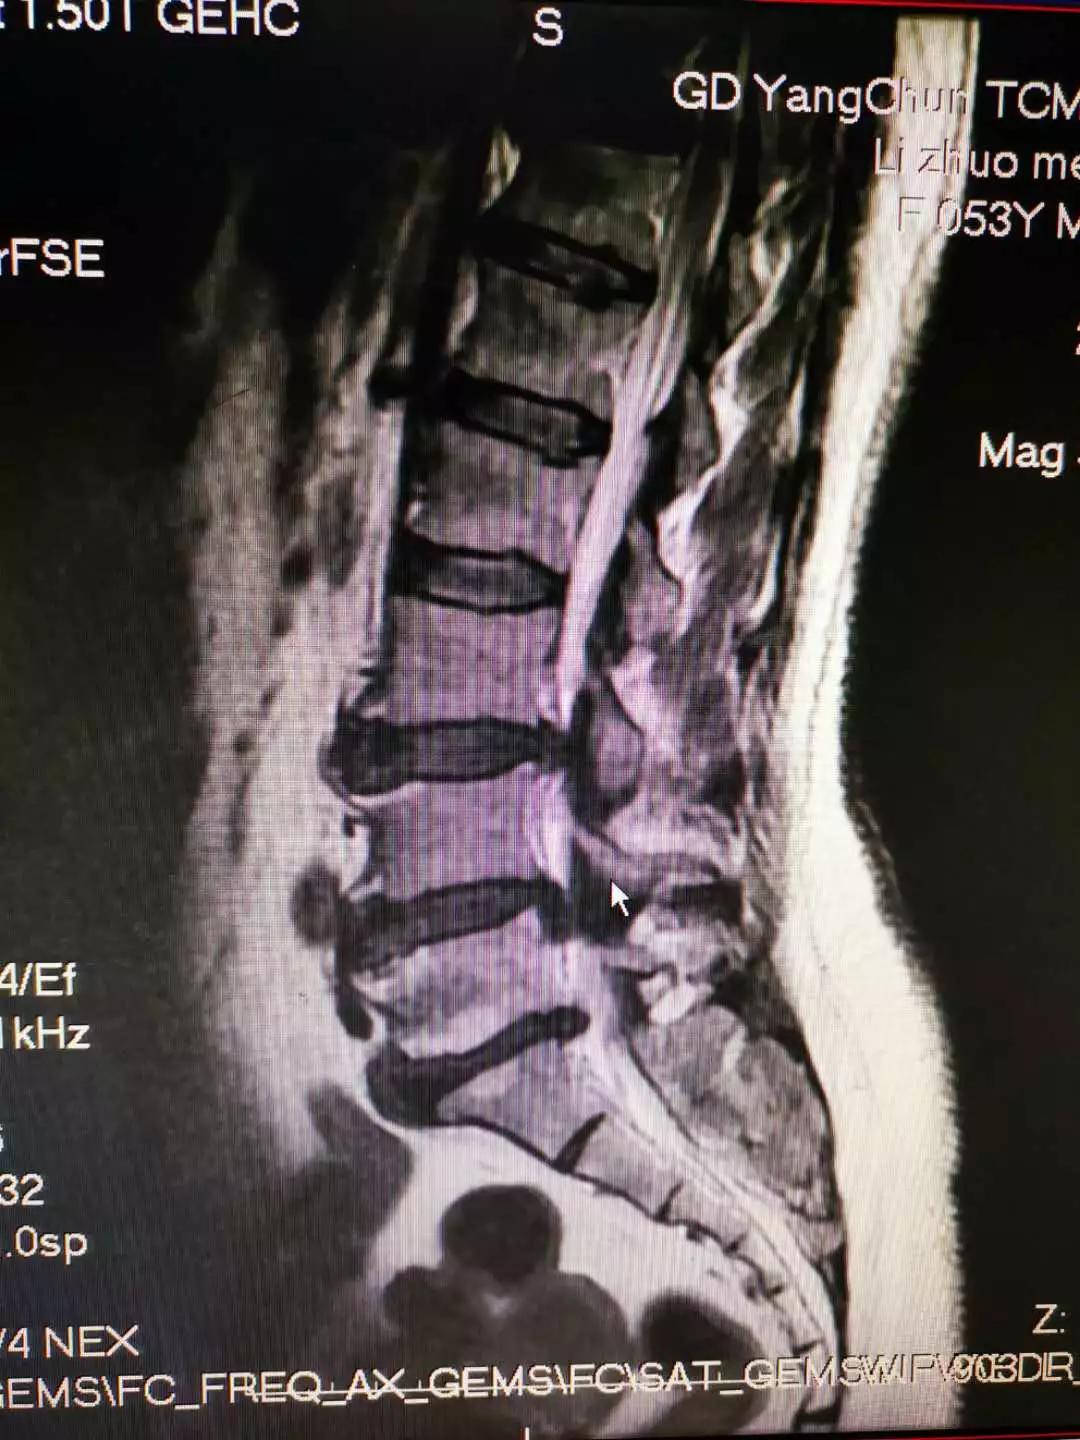

术前磁共振图片见患者腰4/5椎间盘右后脱出